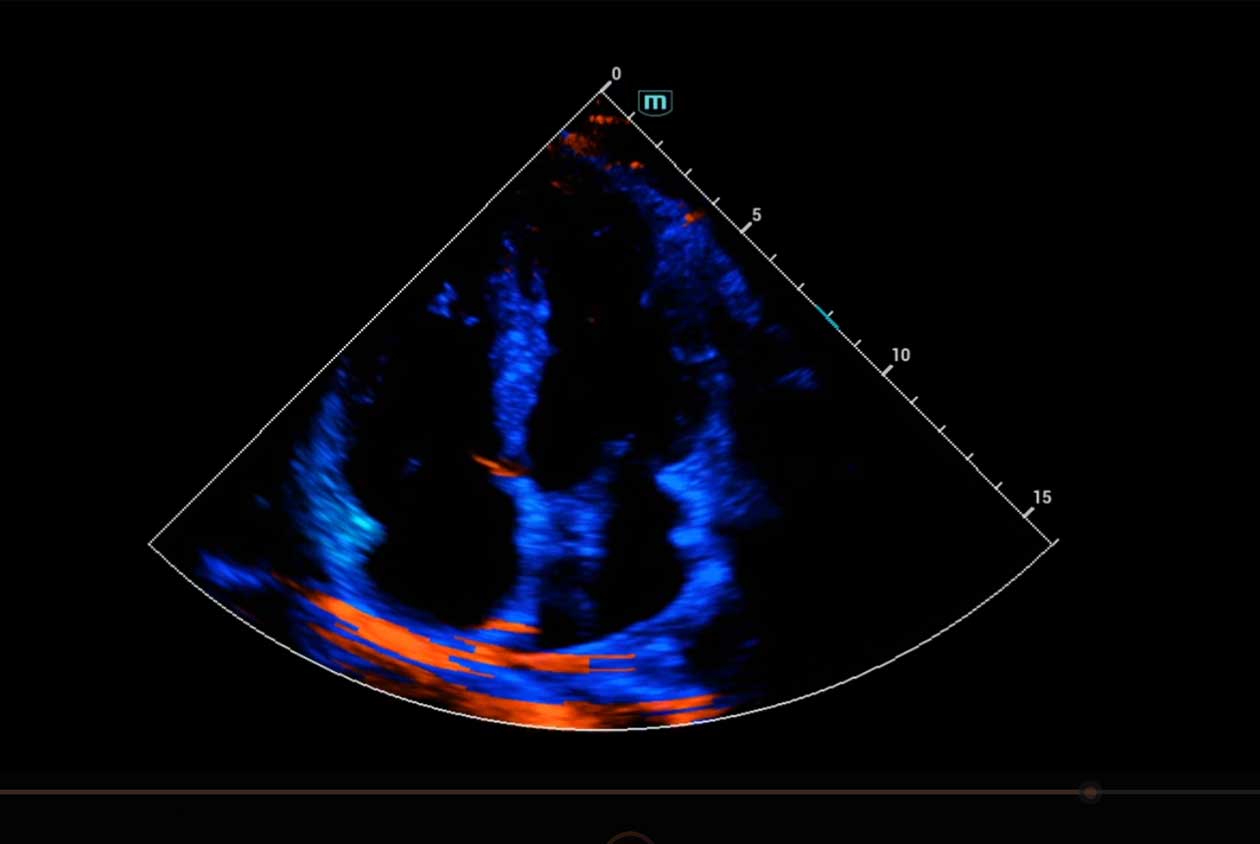

Clinical Images